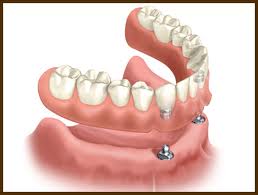

• Σταθεροποιούν τις οδοντοστοιχίες.

• Όταν λείπουν όλα τα δόντια. Τα εμφυτεύματα χρησιμοποιούνται για να συγκρατούν σταθερή την οδοντοστοιχία στο στόμα.